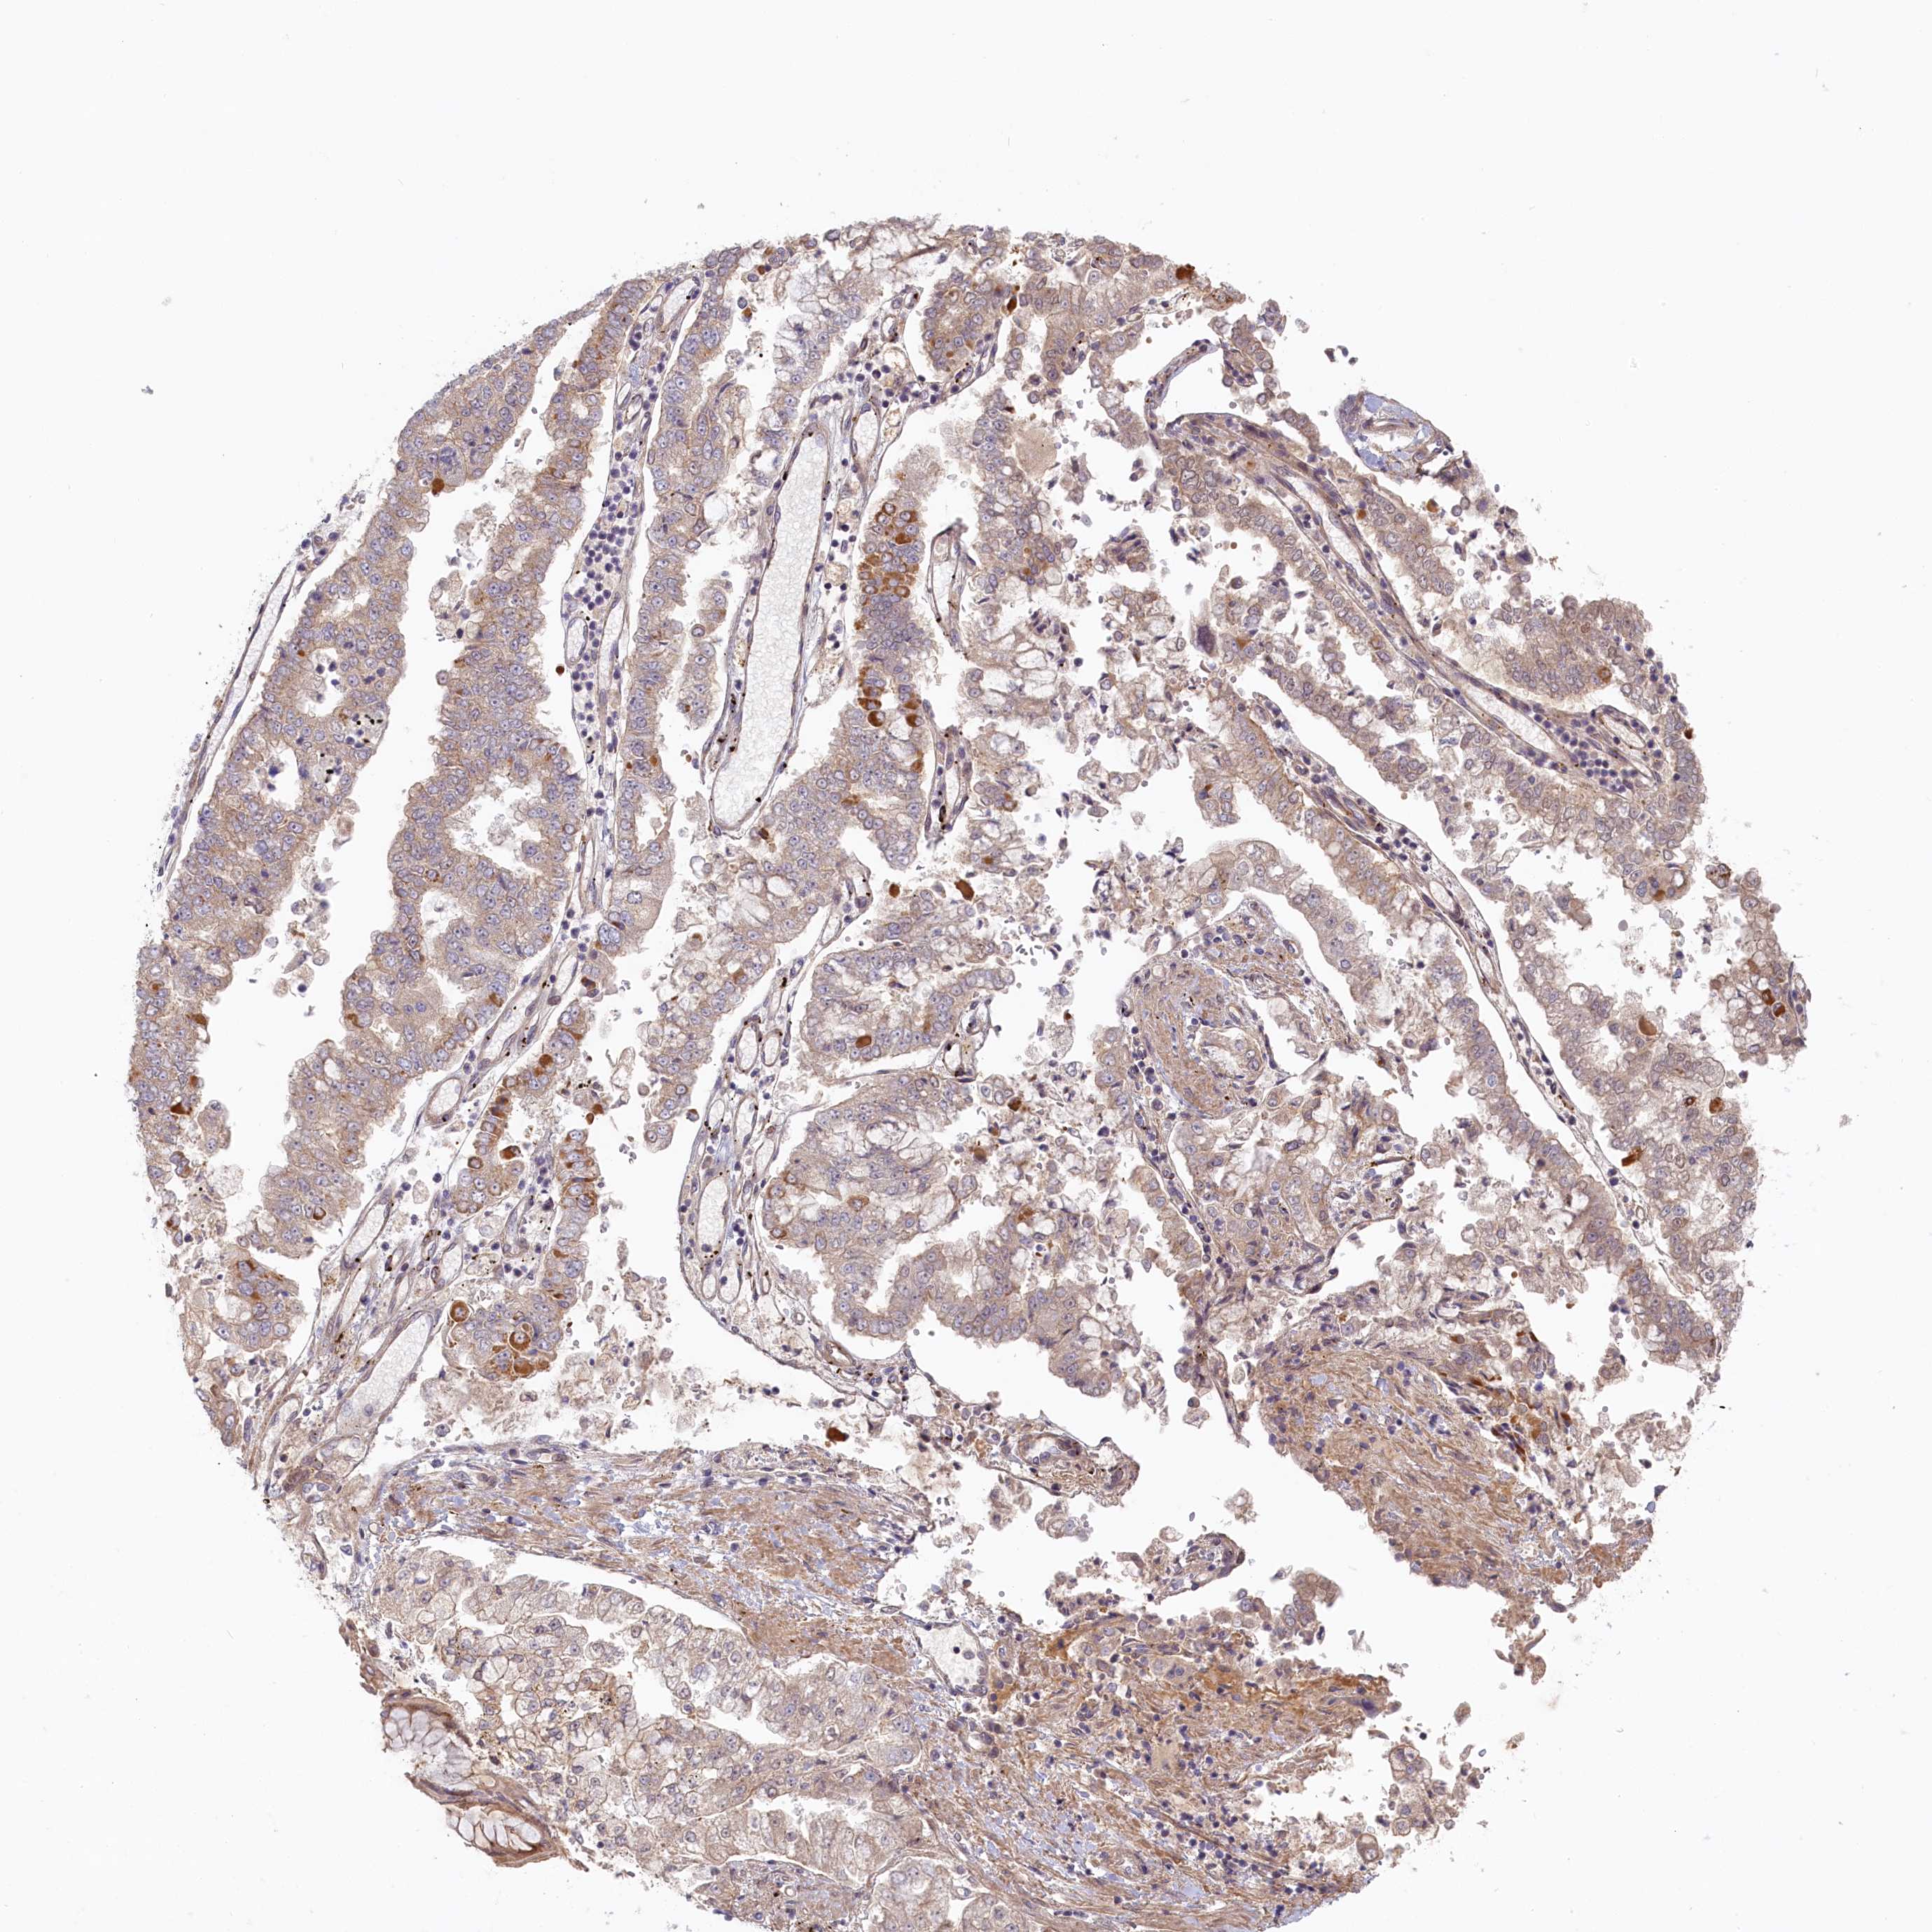

STOMACH CANCER - Protein expressioni

A mouse-over function shows sample information and annotation data. Click on an image to view it in a full screen mode. Samples can be filtered based on level of antibody staining by selecting one or several of the following categories: high, medium, low and not detected. The assay and annotation is described here.

Note that samples used for immunohistochemistry by the Human Protein Atlas do not correspond to samples in the TCGA dataset.

Antibody stainingi

Antibody staining in the annotated cell types in the current human tissue is reported as not detected, low, medium, or high, based on conventional immunohistochemistry profiling in selected tissues. This score is based on the combination of the staining intensity and fraction of stained cells.

Each image is clickable and will lead to virtual microscopy that enables deeper exploration of all samples and also displays staining intensity scores, fraction scores and subcellular localization as well as patient and tissue information for each sample.

Antibody HPA041019

Antibody HPA042033

Staining

High

Medium

Low

Not detected

Intensity

Strong

Moderate

Weak

Negative

Quantity

>75%

75%-25%

<25%

None

Location

Nuclear

Cytoplasmic/membranous

Cytoplasmic/membranous,nuclear

Adenocarcinoma, NOS